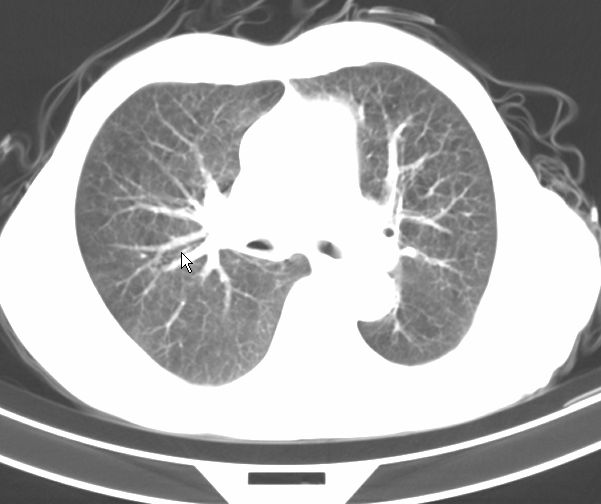

请大家看看是什么性质的。炎性病变首先考虑哪一种炎症。

支持右肺上叶前段\\下叶内基底段感染,建议抗炎治疗后复查,除外结核.

支持右肺上叶前段\\下叶上段感染,建议抗炎治疗后复查,除外结核.

支持右肺上叶前段、下叶内基底段感染,建议抗炎治疗后复查,除外结核.

右肺上叶前段及下叶内基底段感染性病变;建议抗炎治疗后复查。

楼主说是炎症,凭啥?典型的周围型肺癌(腺癌可能性大),肝内可能已有转移,强化看看吧。